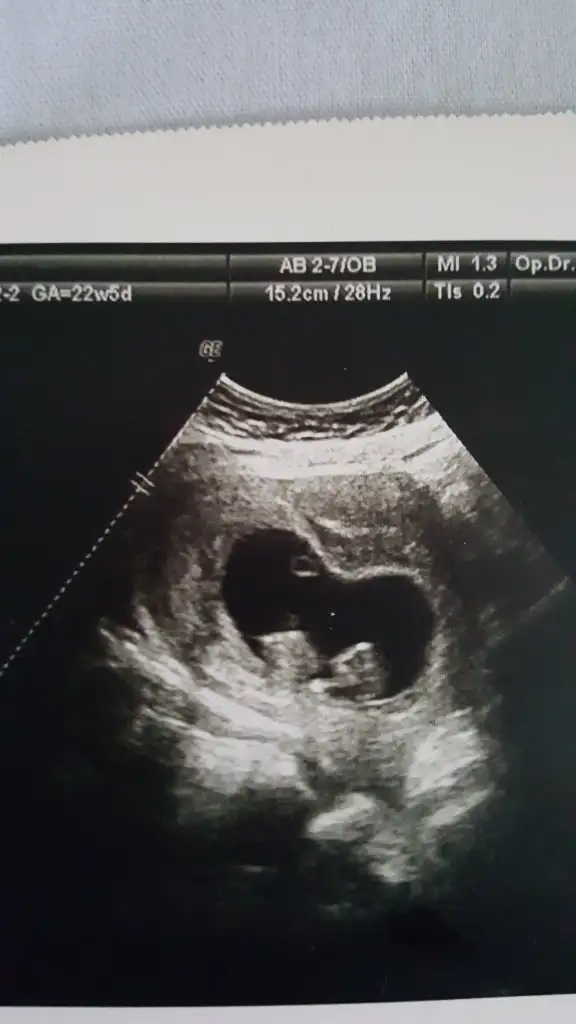

dr soylemeden siz gorun genital nub teorisi ( bebegin cinsiyeti)

13+5 ultrason görüntüsü, bizi de tahmin eder misiniz :)